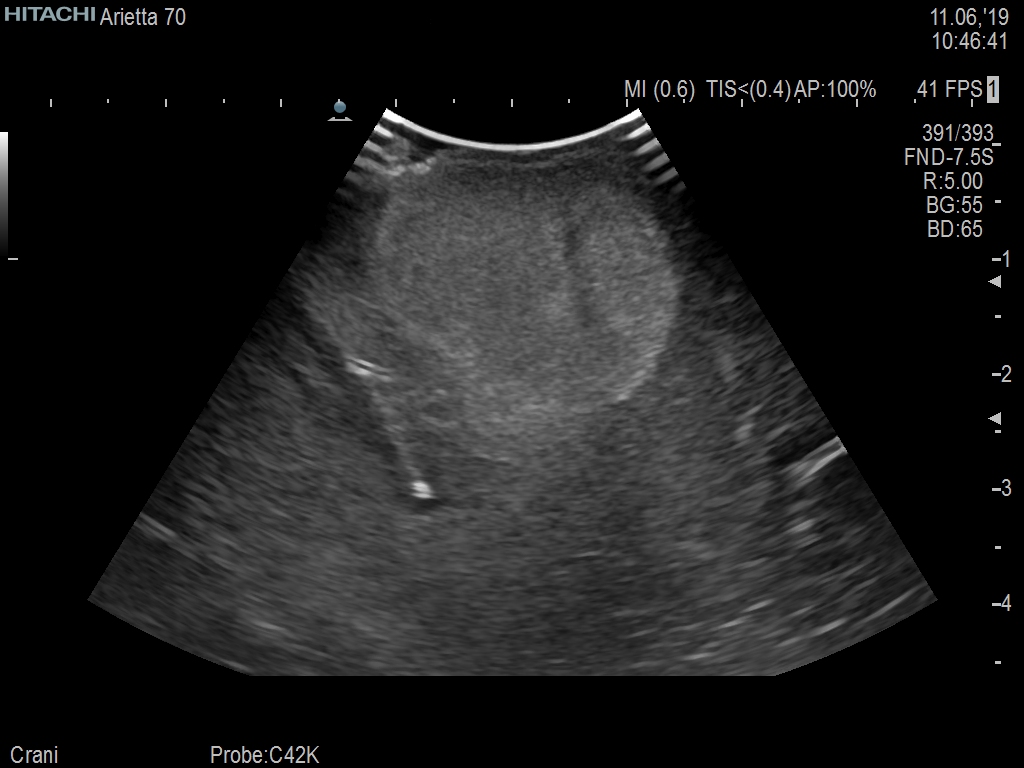

Arietta 70

Recognized for our outstanding image quality, outstanding system reliability and intuitive use of cutting edge technology, Fujifilm Healthcare remains the standard in the field of Surgery.

Learn moreArietta 70

Recognized for our outstanding image quality, outstanding system reliability and intuitive use of cutting edge technology, Fujifilm Healthcare remains the standard in the field of Surgery.